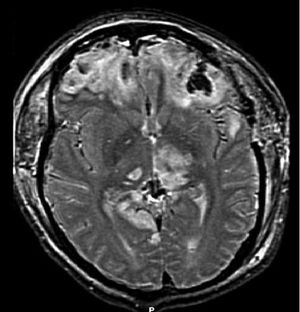

자기공명영상(MRI)은 CT보다 더 자세한 정보를 보여주며 장기적인 예후에 대한 정보를 추가할 수 있다.[162] 특히 확산성 축삭 손상과 같은 손상 특징을 감지하는 데 CT보다 유용하다.[193] 하지만 MRI는 응급 상황에서는 출혈 및 골절 감지의 상대적 비효율성, 영상 획득 시간이 길다는 점, 기계 내 환자의 접근성 문제, 응급 치료에 사용되는 금속 물체와의 비호환성 등의 이유로 잘 사용되지 않는다.[162] 2012년 이후 MRI의 변형 기술로 고해상도 섬유 추적(HDFT)이 있다.[72]

광범위 손상은 신경 영상 연구에서 명백한 손상이 거의 없이 나타나지만, 사후 현미경 기법을 통해 병변을 볼 수 있으며,[18][19] 2000년대 초 연구원들은 백색질 다발을 보여주는 MRI 이미지를 처리하는 방법인 확산텐서영상(DTI)이 확산성 축삭 손상의 정도를 표시하는 효과적인 도구임을 발견했다.[20][21] 광범위 손상으로 간주되는 손상 유형에는 부종(팽창), 뇌진탕 및 확산성 축삭 손상이 포함되는데, 이는 축삭을 포함한 광범위한 손상이며, 백색질 다발과 대뇌피질로의 돌기를 포함한다.[22][23]3. 증상